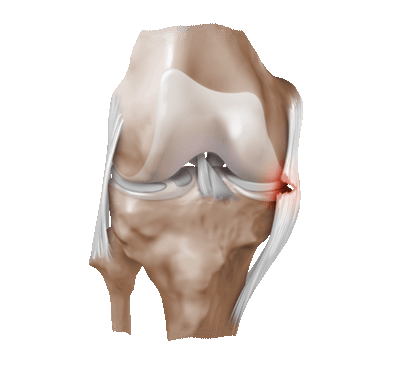

Привычный (рецидивирующий) вывих надколенника – это неестественное состояние, характеризующееся рецедивирующими латеральными (наружными) подвывихами и вывихами надколенника.

Латеральный вывих надколенника характеризуется разрывом медиального ретинакулюма (медиальной пателло-феморальной связки) коленного сустава. Повторный вывих у пациента — главный признак не выполнения медиальной пателло-феморальной связкой своих функций из-за перерастяжения после первичной травмы.

Часто предпосылкой к формированию латеральной нестабильности надколенника становится дисплазия феморопателлярного отдела — врожденного состояния, характеризующегося нарушениями соотношений между надколенником и недостаточно выраженной межмыщелковой бороздой бедренной кости (см. рис.).

Наличие дисплазии различной степени выраженности ведет к тому, что движения надколенника при сгибании и разгибании в коленном суставе происходят с тенденцией к его латеральному смещению. При дополнительном травматическом воздействии это приводит к возникновению полноценного вывиха.